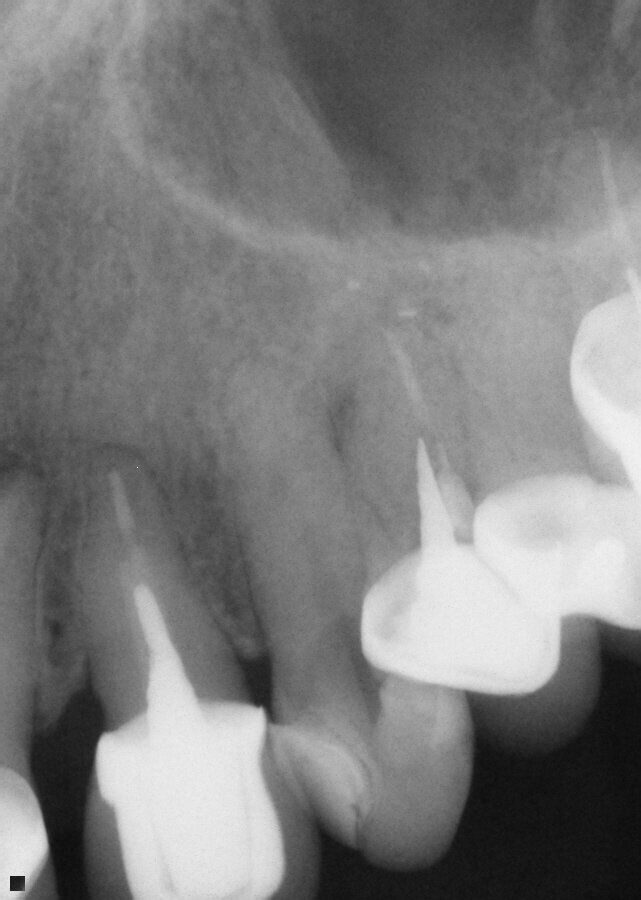

Fig. 14: Patient presented with complaint of pain on chewing on teeth 14 and 15 with increasing sensitivity to hot.

A 37-year-old male new patient presented with the complaint of pain with hot foods and beverages on teeth 14 (maxillary left first molar) and 15 (maxillary second molar) that had been increasing the past six months since he had restorations placed due to decay by the prior dentist before relocating to my area. A radiograph was taken, and slight apical widening was noted on both teeth (Fig. 14). Both teeth were responsive to testing with heat and cold that lingered for a minute or two after the stimulus was removed. Both teeth also tested to slight responsiveness to percussion stimuli. Patient was informed that based on what presented it was recommended that both teeth were moving toward needing endodontic treatment or we could adjust the occlusion and see if that helped with symptom improvement. The patient indicated due to the increasing sensitivity to hot foods and beverages he would prefer to initiate endodontic treatment at this time.